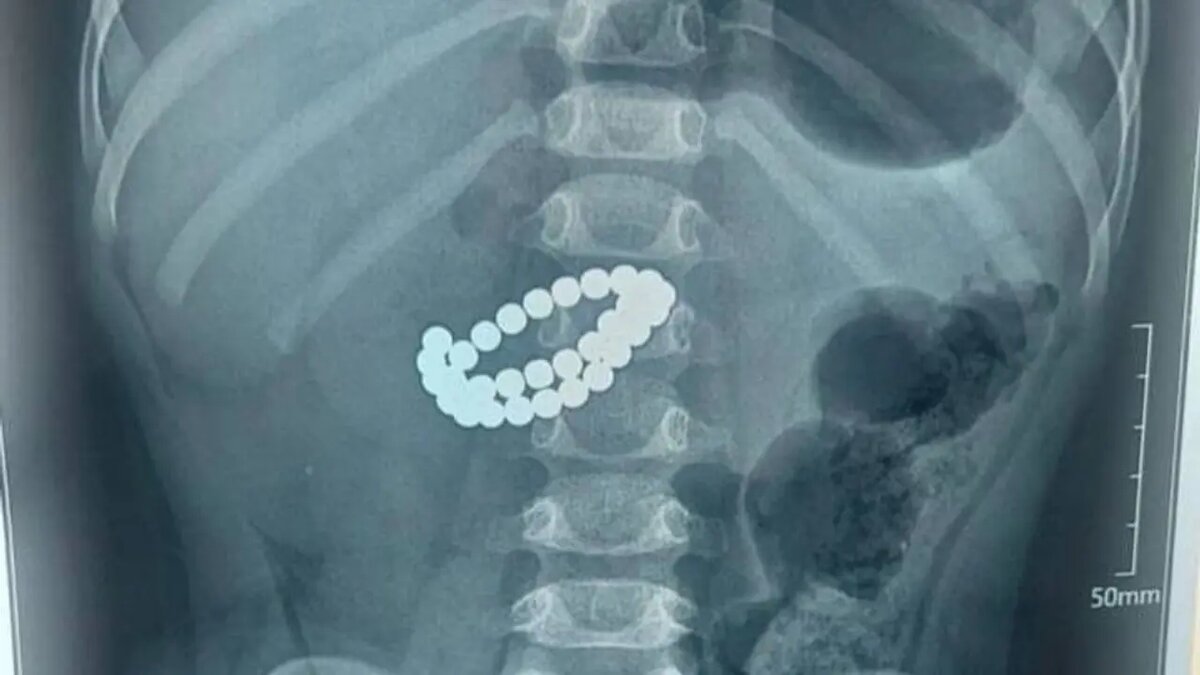

В Казахстане ребёнка, проглотившего 31 магнит, спасли операцией

Во время обследований выяснилось, что в кишечнике ребёнка находится множество магнитов. Врачи отметили, что в нескольких местах тонкого кишечника образовались перфорации, а в брюшной полости усиливалось воспаление. В такой ситуации время — не “золото”, а напрямую вопрос жизни и смерти.

Специалисты заявили, что единственным способом спасти ребёнка была срочная операция. Хирурги методом лапаротомии вскрыли брюшную полость, извлекли магниты, ушили повреждённые участки, очистили брюшную полость и установили дренаж.

Самое опасное в том, что даже если магниты были проглочены по отдельности, внутри кишечника они притягиваются друг к другу. Между ними зажимается стенка кишечника, нарушается кровообращение, ткани повреждаются, образуются отверстия, и за короткое время может развиться перитонит.